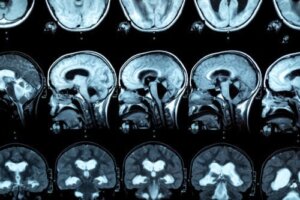

En hjerne.

Hjernebjelken ligger i det sentrale området av hjernen. Det er en anatomisk struktur som forbinder de to halvdelene.